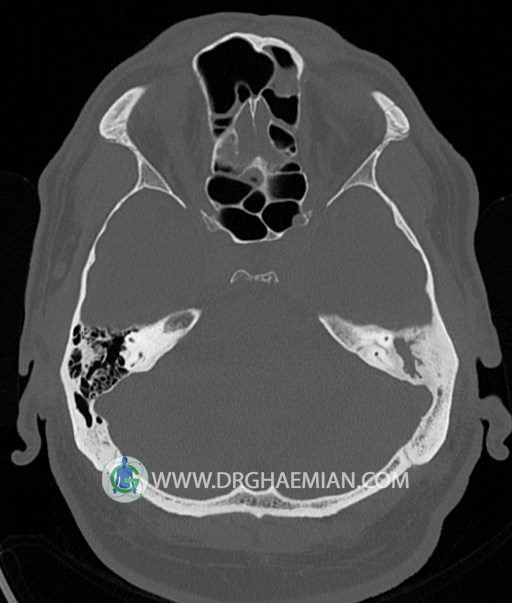

سی تی اسکن گوش داخلی به رادیولوژیست اجازه می دهد تا سطوح مختلف، یا اسلایس هایی از استخوان های که از جمجه به گوش می روند را از طریق امواج ایکس چرخشی مشاهده کند. در این کیس اودیت مدیا، ماستوئیدیت مزمن، اوتیت خارجی، انحراف سپتوم بینی، کونکا بولوزا و افزایش ضخامت سینوس ها مشاهده می شود.

گزارش پزشک :

در HRCT از استخوان تمپورال با مقاطع آگزيال ، ساژيتال و کرونال ظريف ( 0.6 mm ) :

– اپاسيتي گوش مياني چپ ناشي از وجود دانسيته نسج نرمي دراطراف استخوانچه ها همراه با اروژن اسکوتوم و

استخوانچه ها بدون جابجايي در رديف استخوانچه ها مشهود است که مطرح کننده اوتيت مديا همراه با نشانه

هاي مشکوک به کولستئاتوم مي باشد .

– اپاسيتي و اسکلروزيس ماستوئيد چپ نشانه ماستوئيديت مزمن

– اپاسيتي کانال گوش خارجي ناشي از دانسيتي نسج نرمي مطرح کننده external otitis